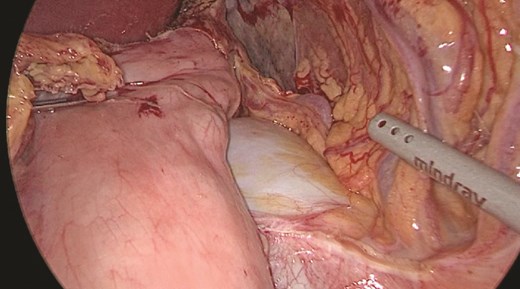

Multidisciplinary discussion was held to evaluate the most appropriate course of action for the patent condition, and the consensus was reached to pursue embolization as a first intervention. Embolization was performed by interventional radiology with no complications post-procedure, and the patient was optimized prior to her procedure. Patient was taken to the operating room in stable conditions. The spleen was enlarged around 20 cm. Inferiorly, the omentum and part of the transverse colon was attached to the spleen (Fig. 3), so we freed the omentum from the splenic tissue. The dissection continued until reaching short gastric vessels and entering the lesser sac (Fig. 4). Once the lesser sac was entered, the splenic vessels were identified (Figs 5 and 6), the splenic vein was hugely dilated with multiple collateral branching vessels at the hilum. Gaining posterior mobilization of the vein was challenging. The splenic artery was tortuous from the insertion around itself (Fig. 7). After complete mobilization of the fundus, we elected to divide each vessel starting with the splenic artery so we can achieve full mobilization of the vein (Fig. 9). After controlling the splenic artery, the splenic vein was dissected proximal to the splenic hilum (Fig. 8). It was hugely dilated and its wall is thickened secondary to AV fistula. It was difficult to achieve circumferential dissection, so we decided at that moment to convert to laparotomy to complete ligating the vein and to retrieve the specimen (Fig. 10a and b).

Anterior portion of the splenic vein seen posterior to the stomach.